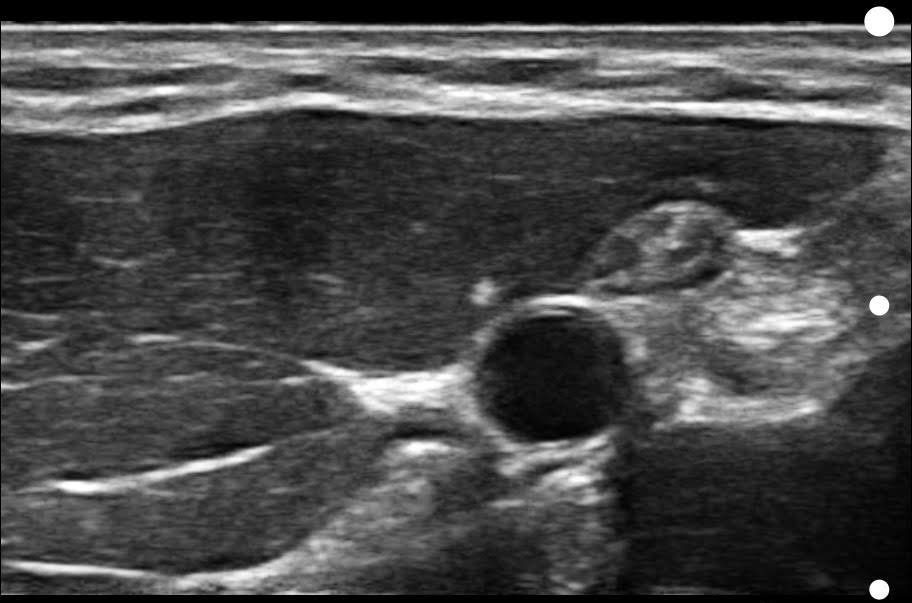

Visualize targets in real time for precise nerve blocks and corticosteroid injections—reducing injectate volumes and boosting safety, confidence, and patient outcomes.

Assess synovitis, enthesitis, and monitor treatment efficacy with high-resolution ultrasound, enabling precise, real-time joint and soft tissue evaluation, accurate needle guidance, and improved confidence in clinical decision-making.